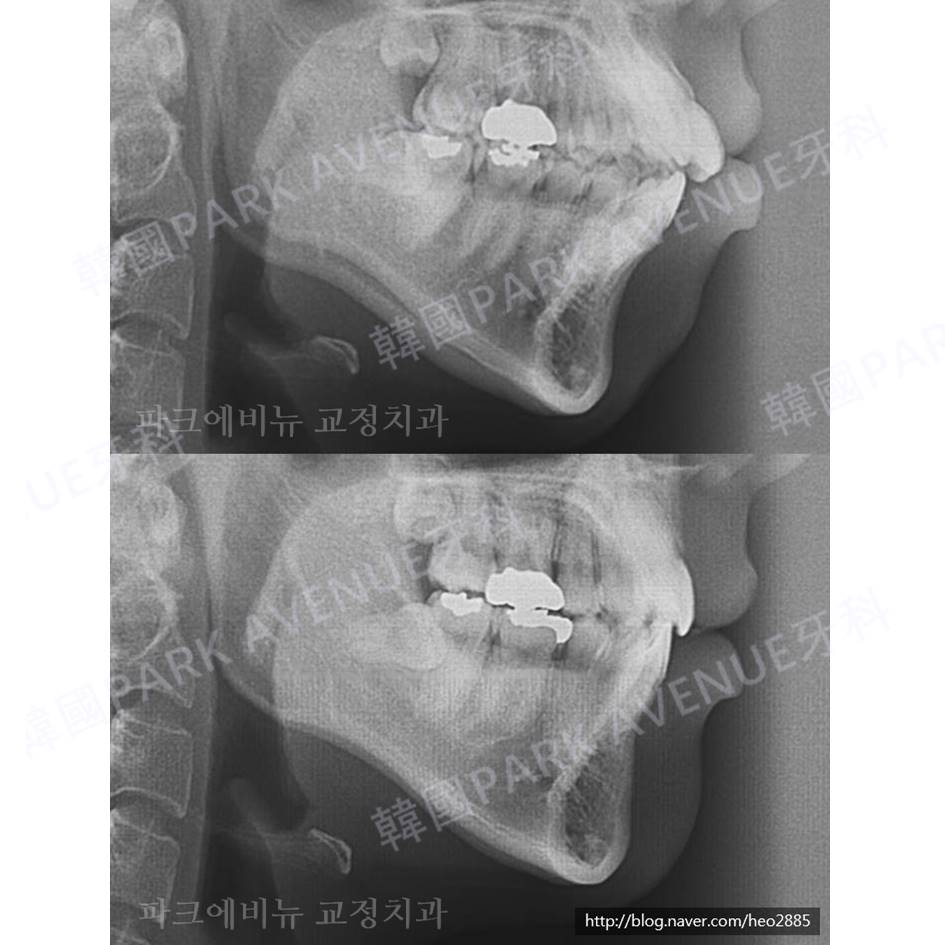

<治疗前后>

最大的形态和下巴线变得特别好!

而且突嘴和无下巴同事改善了。

过度的牙龈露出度也显著减少了。

简单的拔牙矫正可以得到这种效果吗?

答案是 “只是简单的矫正 不!可!能!”

我们可以看以上面牙齿的上方移动

下巴逆时针反向回转时下巴低移动到前方。

矫正治疗是治疗结束以后要维持咬合也是非常重要。

治疗后过了六年十个月特别好好维持排列和咬合